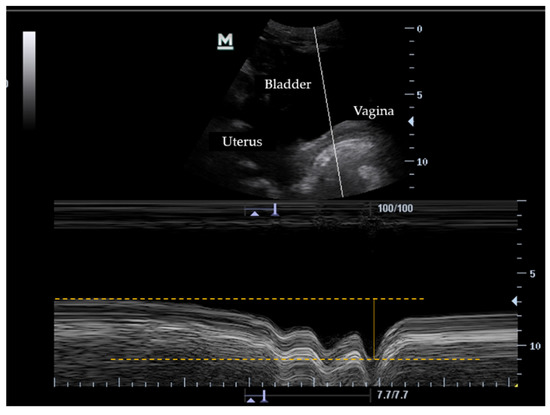

2.4. Data Collection